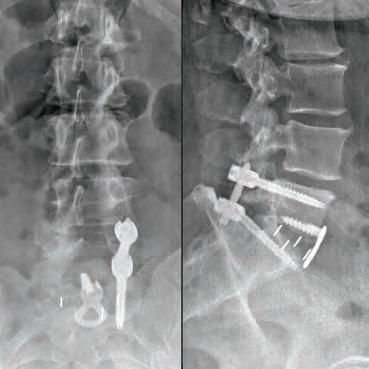

Inspired by the patients he’s cared for there, Dr. Courtney made education a priority. He was salutatorian of his high school class and went on to graduate summa cum laude from Northeast Louisiana University. While at Louisiana State University Medical School, he utilized his summer to perform spine biomechanical tests on human spine cadavers utilizing pedicle screws. Considered cutting edge biomechanics and technology at that time, most spine surgeons didn’t even know they existed yet. However, Dr. Courtney performed one of the first biomechanical tests on those implants. It was a feat that earned him the Howmedica Biomechanic Award and the Louisiana Orthopedic Association Award. He also placed fourth in the World Congress for Student Research Competition.

This realization inspired Dr. Courtney to design, develop, biomechanically test, complete FDA testing and oversee quality control and validation on a host of tools he created. To date, Dr. Courtney has developed nine spinal product lines and obtained nine patents and 14 trademarks on spine related products.

Led by Dr. Courtney, the skilled team at Advanced Spine Center cares for patients with neck and back pain using a wide array of the most state-of-the-art tools and techniques—from conservative physical therapy and injection therapy—to advanced pain manage-

ment, as well as surgical intervention. We employ the latest in minimally invasive spine surgeries, in addition to cutting-edge replacement technology. Incorporating both high tech and high touch, we get our valued patients back to their lives so they can enjoy all the activities they love.

SURGERY: C4/C5, C5/C6, C6/C7 ACF (ANTERIOR CERVICAL FUSION)

“Great medicine coupled with great care. Dr. Courtney takes the time to listen to your medical needs. He put me at ease regarding my condition.”